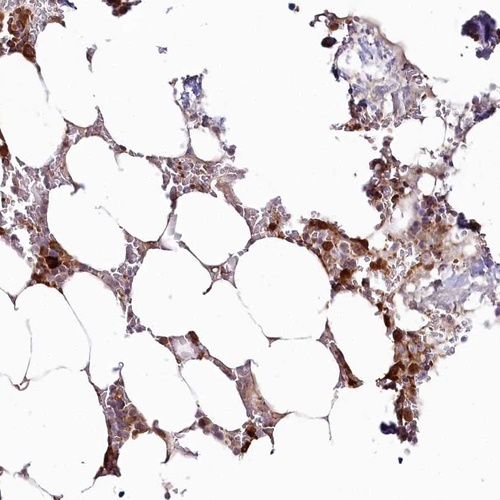

Immunohistochemical staining of human bone marrow shows strong cytoplasmic positivity in hematopoietic cells.